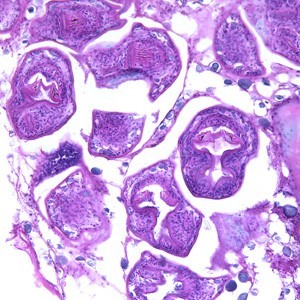

寄生虫病